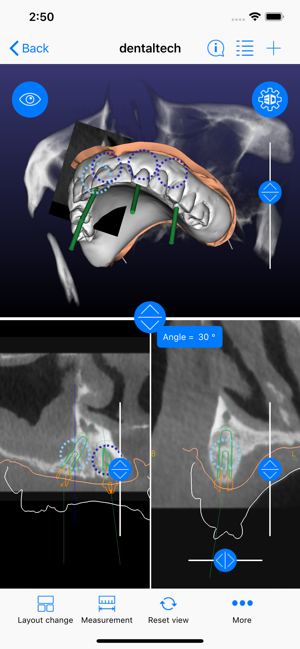

ICX-Magellan X is a cloud-based Software concept used for CBCT-Analysis and to create Implant-Treatment plans.

The ICX-Magellan X App completes this System primarily regarding communication, treatment-plans that were prepared at the pc can be shared with other users in real-time, commented, changed or confirmed.

The App can be integrated supporting any workflow; existing treatment-plans can be recalled, edited or used for patient-education anywhere anytime.